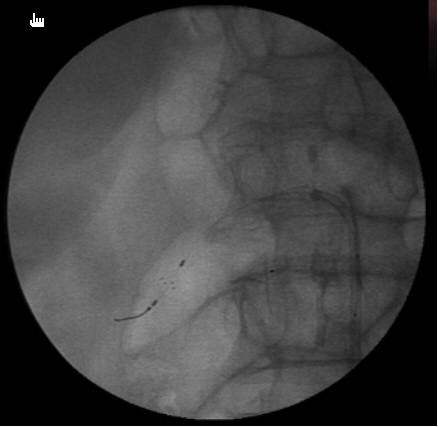

- Once the stent is deployed, a completion-angiogram is done to conform the proper placement of the stent and to make sure there has been no residual stenosis (Figure 3). It is important to make sure the renal ostium is properly covered by the stent or else it may undergo re-stenosis.